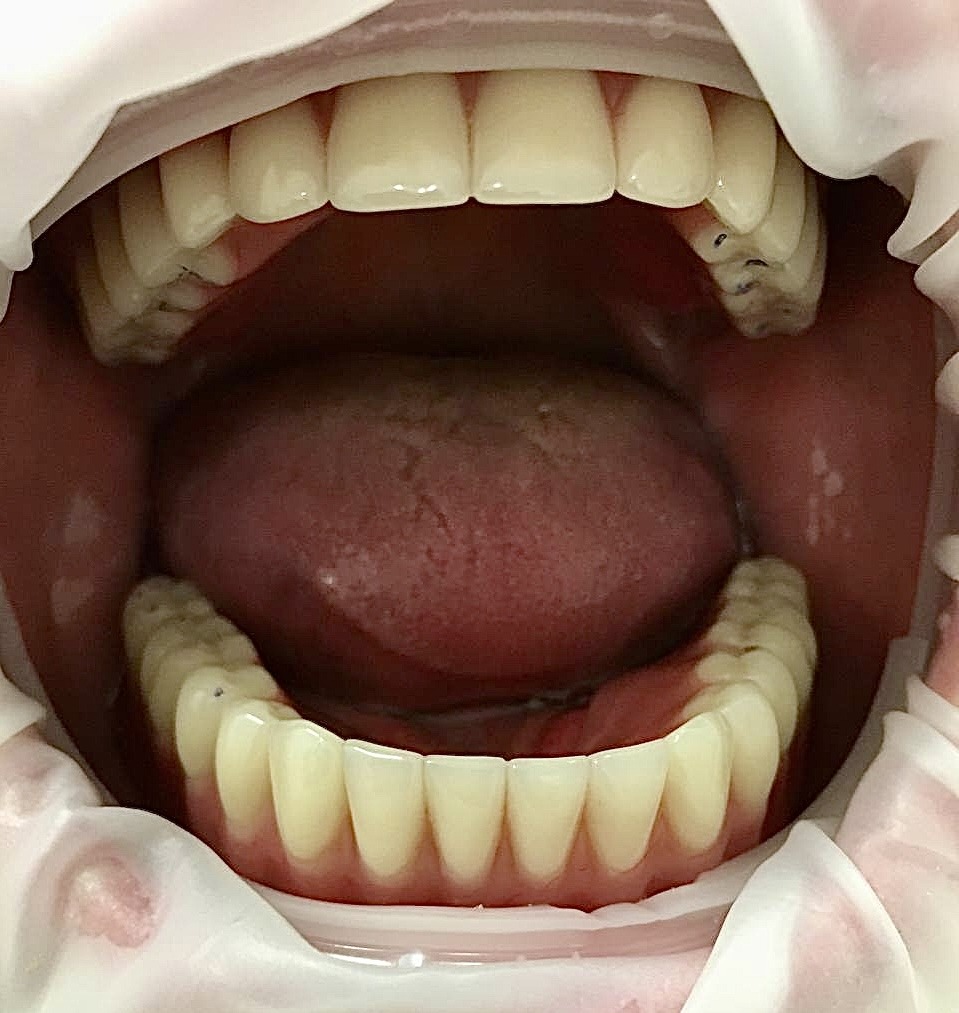

После

Были установлены имплантаты на верхней и нижней челюсти. С опорой на имплантаты смоделированы балочные конструкции, на которых установлены рельсовые аттачмены для дополнительной фиксации съемных протезов. При этом пациент сохраняет возможность самостоятельно снимать и одевать протезы, осуществлять их гигиену.